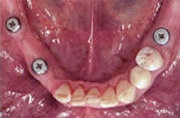

Heute

Ersatz der Unterkiefer-Seitenzähne beidseits mit natürlich aussehenden, festsitzenden Brücken und Kronen auf Implantaten.